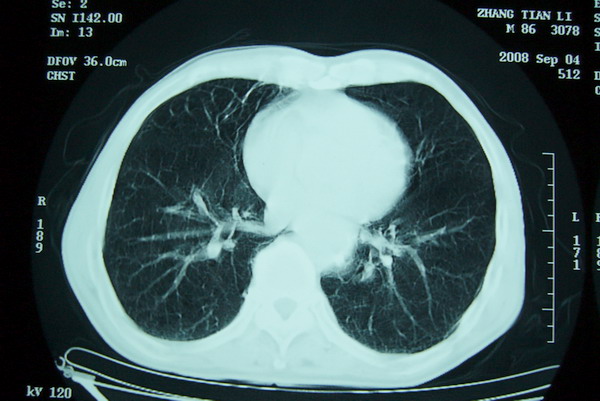

标题: CT15579:男 86岁 咳嗽 咳少量白痰 发热2天 吸烟史60年 [打印本页]

标题: CT15579:男 86岁 咳嗽 咳少量白痰 发热2天 吸烟史60年

右上周围型肺癌,慢支,肺气肿。

分叶及少量边缘性钙化,老年人,周围性肺癌首先考虑。

右上肺一不规则团块,边缘有分叶和毛刺,纵隔有淋巴结肿大。右肺周围性肺癌首先考虑。